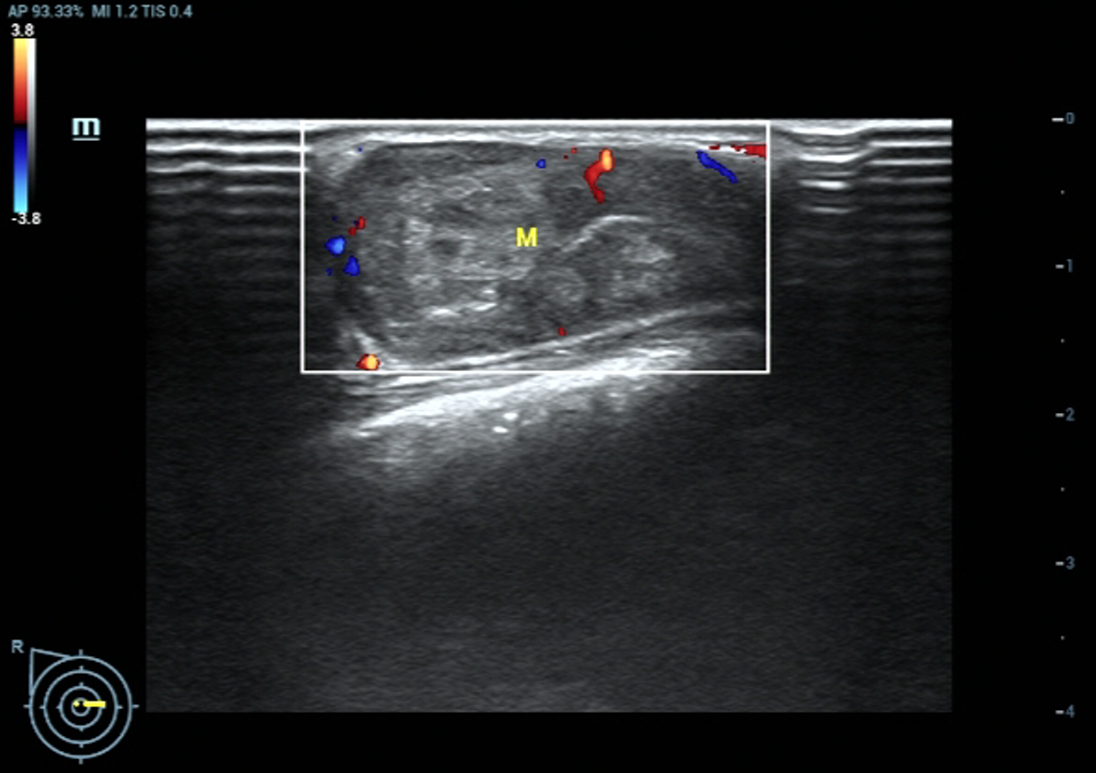

1、单孔腔镜乳腺纤维瘤/良性纤维上皮性肿瘤区段切除术

图片 3.png

手术病例均为女性,年龄在16-67岁之间,双侧乳腺良性肿瘤3例,左侧乳腺良性肿瘤3例,右侧乳腺良性肿瘤2例,肿瘤最长径在3.6-8.2cm之间,切口位置均选择隐蔽在腋窝皮肤皱襞,长度约2.5cm,病理结果为乳腺纤维腺瘤、良性纤维上皮性肿瘤或良性叶状肿瘤。

微信图片_20221202184457.jpg